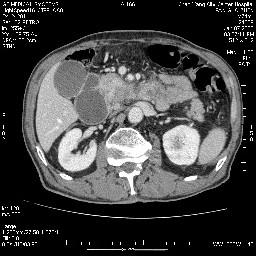

女,74岁,呕吐10余日

壶腹部的占位性病变,考虑为十二指肠癌并梗阻,但脾内多发性低密度区为转移吗?

还有胃、脾之间可见有侧支循环建立。左肾盂积水。

考虑来源于十二指肠水平段的恶性占位,侵及周围组织,特别是胰腺,可见区域淋巴结肿大,左侧下腔静脉畸形。

十二指肠水平段腔内占位伴梗阻,中等度较为均匀的强化,洗脱慢,区域淋巴结显示增多,符合腺癌表现。下腔静脉变异。

十二指肠降段扩张,水平段狭窄成鼠尾状,肠壁明显增厚,胰腺勾突增大成不均匀强化,其内可见低密度区,胆囊增大,1十二指肠水平段腺癌侵犯胰腺勾突可能大,2胰腺癌侵犯十二指肠(只有胆囊增大没有肝内外胆管扩张不好解释)代除外.

十二指肠降段扩张,水平段狭窄成鼠尾状,肠壁明显增厚,胰腺勾突增大成不均匀强化,其内可见低密度区,胆囊增大,1十二指肠水平段腺癌侵犯胰腺勾突可能大,2胰腺癌侵犯十二指肠 。

今日手术结果:胰腺钩突癌侵犯十二直肠,腹腔淋巴结转移.